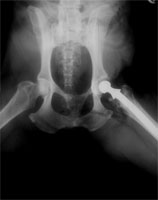

Hftgelenksprothese  Hund

Hftgelenksprothese beim Schferhund